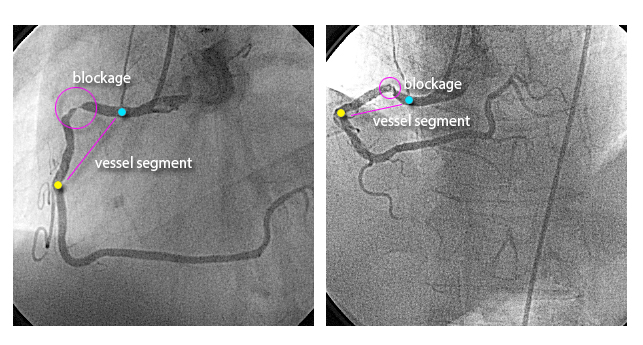

In the angiographic example below, two images of the same artery, focusing on the same arterial segment, can potentially give misleading information of blockage length and severity.

These imaging based mistakes may lead to repeat procedures and serious clinical complications.